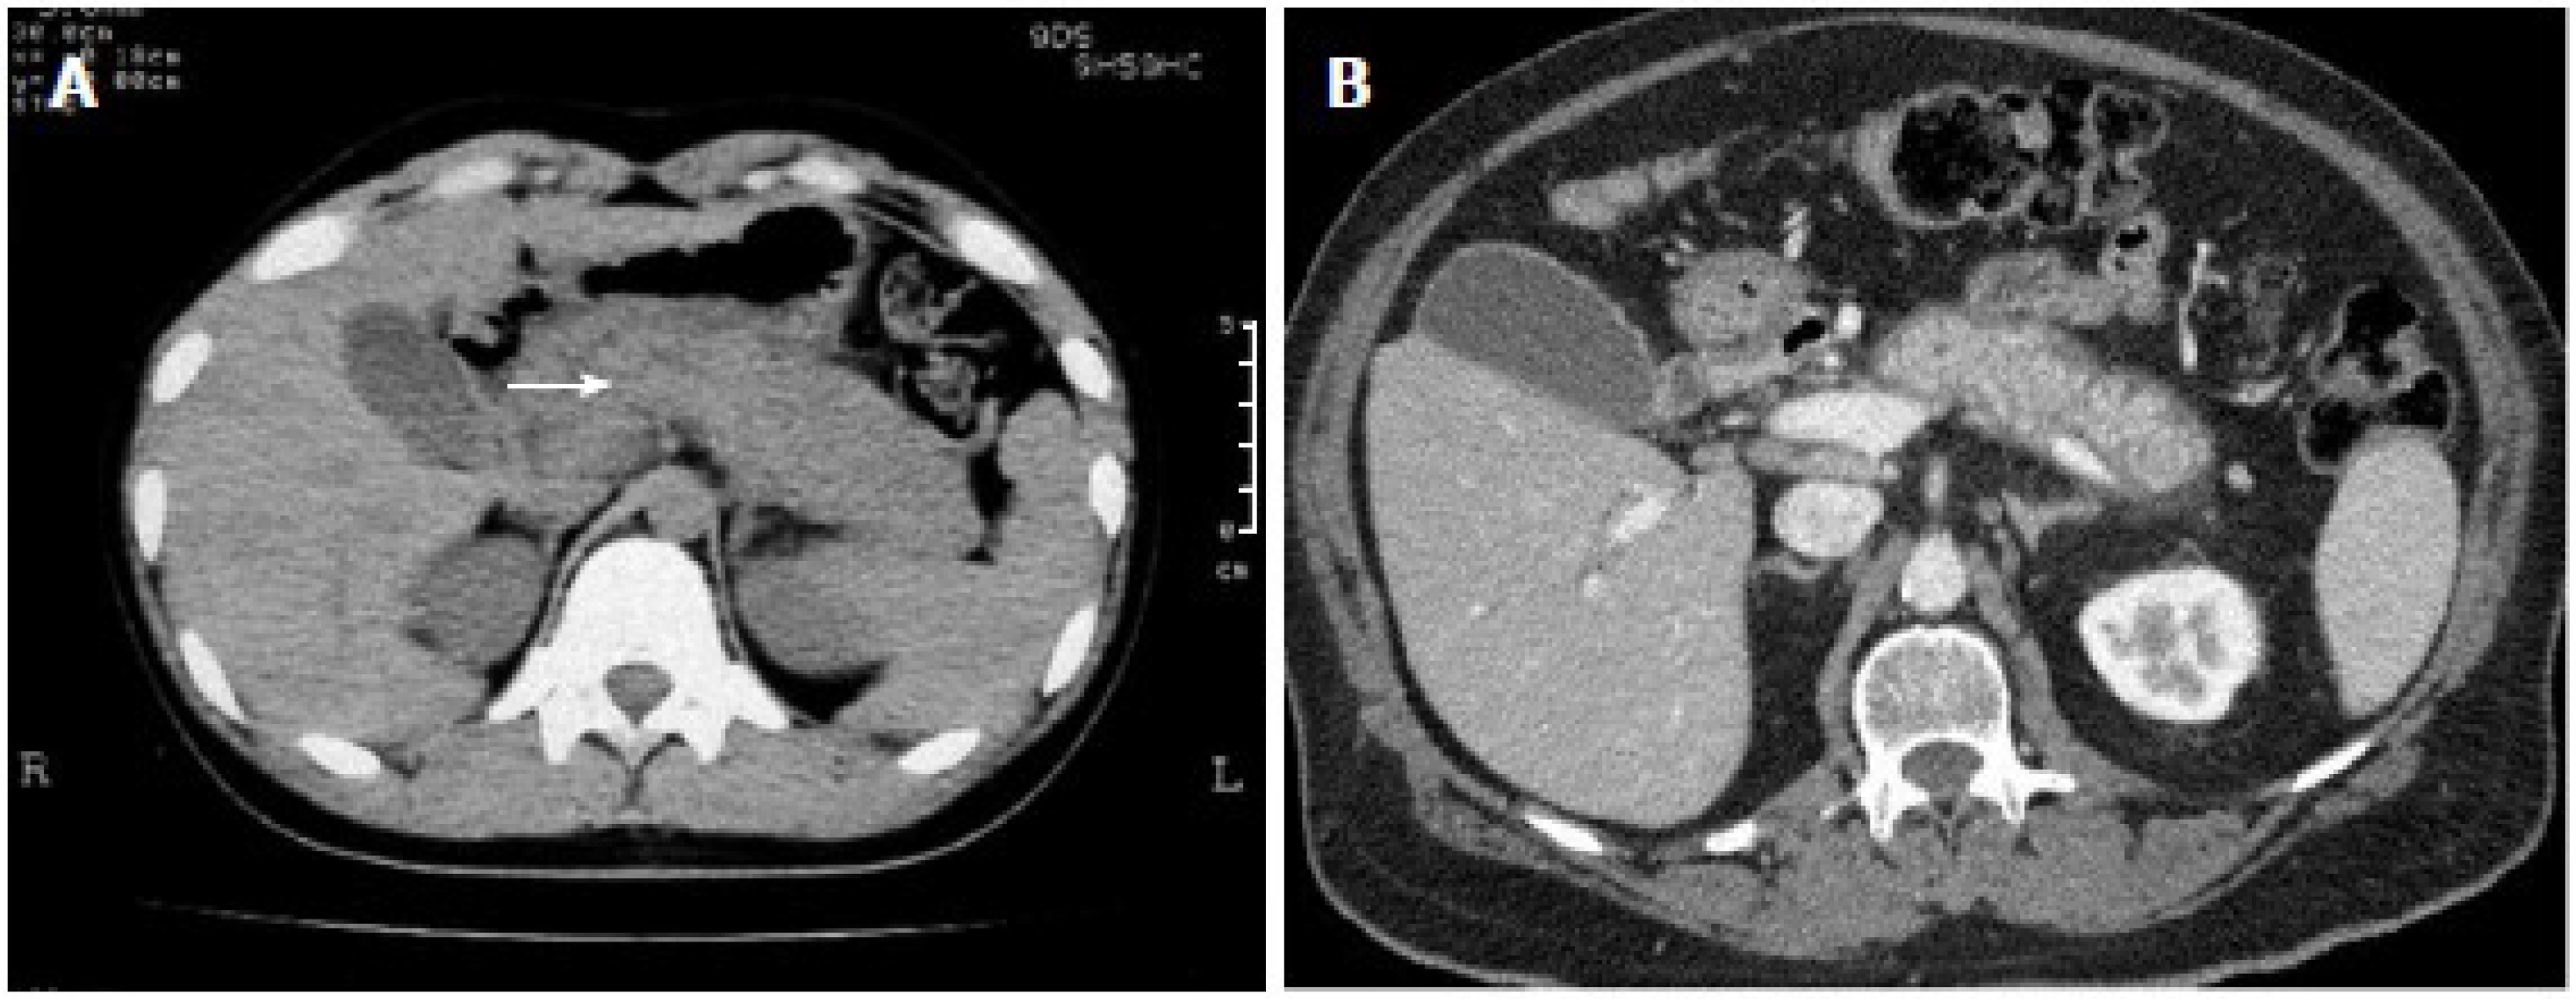

5.1. Radiographic Findings

- Rehnitz, C.; Klauss, M.; Singer, R.; Ehehalt, R.; Werner, J.; Büchler, M.W.; Kauczor, H.-U.; Grenacher, L. Morphologic patterns of autoimmune pancreatitis in CT and MRI. Pancreatology 2011, 11, 240–251. [Google Scholar] [CrossRef]

- Lee, S.; Kim, J.H.; Kim, S.Y.; Byun, J.H.; Kim, H.J.; Kim, M.-H.; Lee, M.-G.; Lee, S.S. Comparison of diagnostic performance between CT and MRI in differentiating non-diffuse-type autoimmune pancreatitis from pancreatic ductal adenocarcinoma. Eur. Radiol. 2018, 28, 5267–5274. [Google Scholar] [CrossRef]

- O’Reilly, D.A.; Malde, D.J.; Duncan, T.; Rao, M.; Filobbos, R. Review of the diagnosis, classification and management of autoimmune pancreatitis. World J. Gastrointest. Pathophysiol. 2014, 5, 71–81. [Google Scholar] [CrossRef]